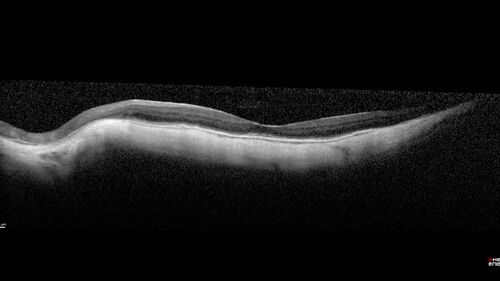

Myopic CNVM Left Eye

80 year old female. VA dropped to 20/125 but improved back up to 20/50 with Vabysmo